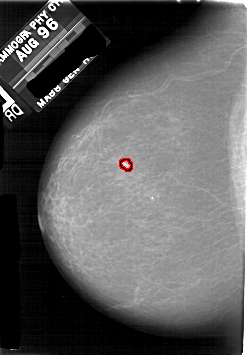

FILE: A_1731_1.LEFT_MLO.OVERLAY

TOTAL_ABNORMALITIES 1

ABNORMALITY 1

LESION_TYPE CALCIFICATION TYPE PLEOMORPHIC DISTRIBUTION CLUSTERED

ASSESSMENT 4

SUBTLETY 2

PATHOLOGY MALIGNANT

TOTAL_OUTLINES 1

BOUNDARY